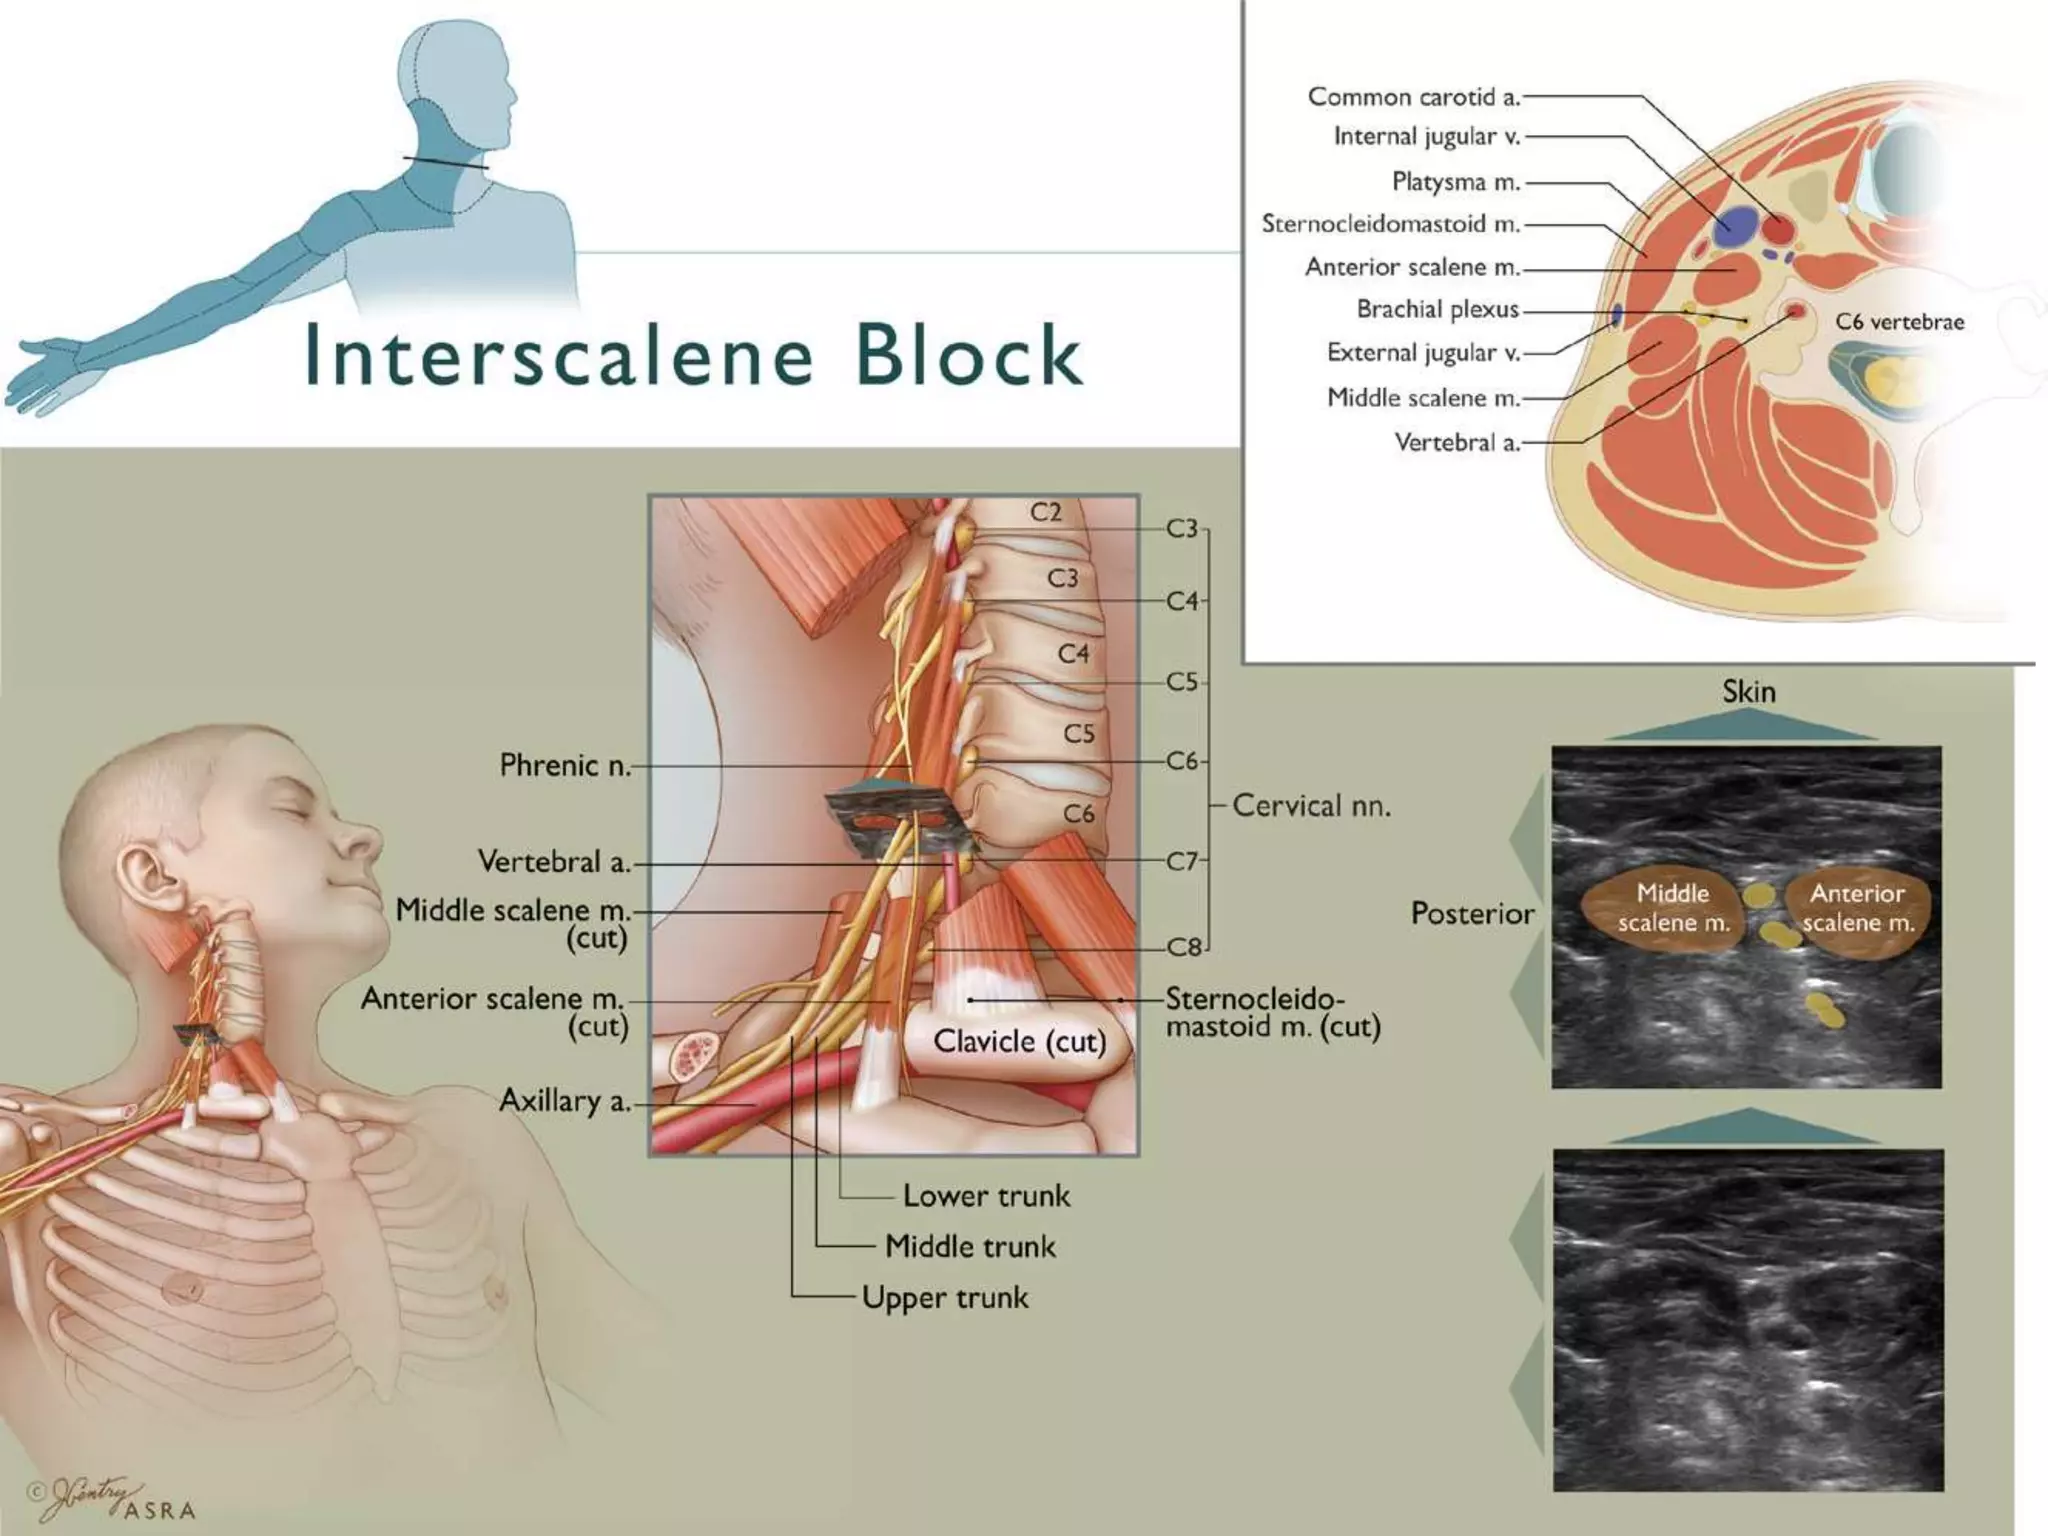

This document provides an overview of brachial plexus anatomy and techniques for brachial plexus nerve blocks. It begins with a description of the brachial plexus formation from cervical and thoracic nerve roots and its branching pattern. Four main approaches for brachial plexus nerve blocks are described: interscalene, supraclavicular, infraclavicular, and axillary. Details are provided on the anatomy and techniques for performing interscalene and supraclavicular brachial plexus blocks. Ultrasound guidance is discussed as an advancement which allows real-time visualization of needle and nerve. Complications are also summarized.